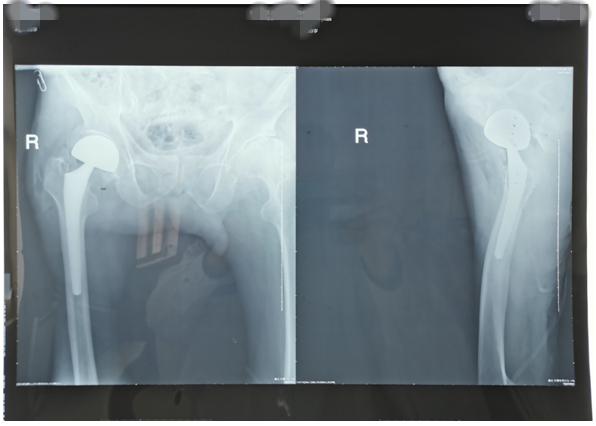

近期,我科又為兩位高齡老人因股骨頸骨折行髖關(guān)節(jié)置換術(shù)。一位是呂大爺,82歲高齡,右髖部外傷后疼痛一個月就診。當時呂大爺外傷后局部疼痛,未引起注意仍日?;顒?,癥狀逐漸加重后就診,既往有高血壓、腦梗塞、腦出血病史,入院后積極完善術(shù)前評估,在無絕對手術(shù)禁忌癥時行右側(cè)股骨頸骨折髖置換術(shù),手術(shù)時間短,出血少,術(shù)后第二天呂大爺扶助步器下床活動,避免了因骨折長時間臥床各種并發(fā)癥的發(fā)生,老人及家屬對我們的治療非常滿意。(見下圖)

右髖正側(cè)位手術(shù)前后對比圖